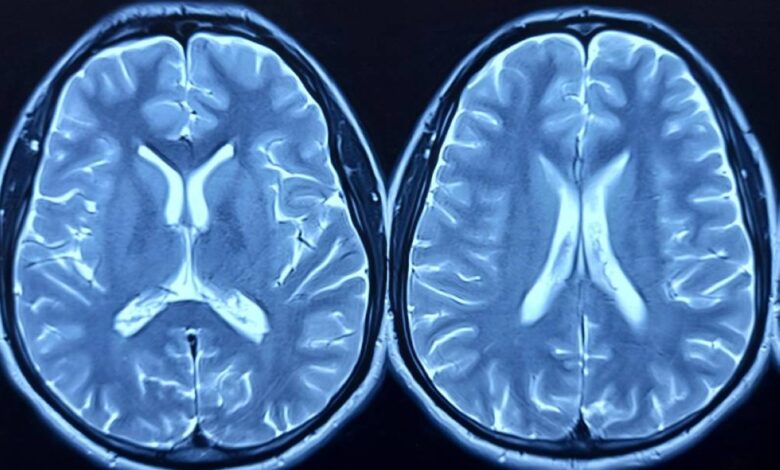

فحص دماغ الأمريكيين من أصل أفريقي يكشف عن مفاجأة

ركزت الدراسة على تحليل التعبير الجيني في أنسجة الدماغ، وهو مقياس يوضح كمية البروتينات التي تنتجها الجينات، بين أشخاص مصابين بالزهايمر وآخرين غير مصابين.